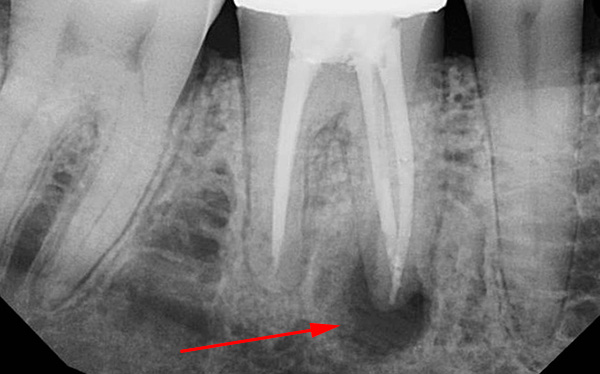

In questi casi, la pinza raramente aiuta a risolvere il problema e un dentista professionista prende ... No, non lo scalpello e il martello. Attualmente, un dentista professionista preferisce approcci moderni per rimuovere tali radici: tagliare con un trapano e rimuovere le radici individualmente con un ascensore e (o) una pinza. Ciò è particolarmente vero per il sesto dente e il dente del giudizio.

Foto di un dente le cui radici sono separate da un trapano prima della rimozione: